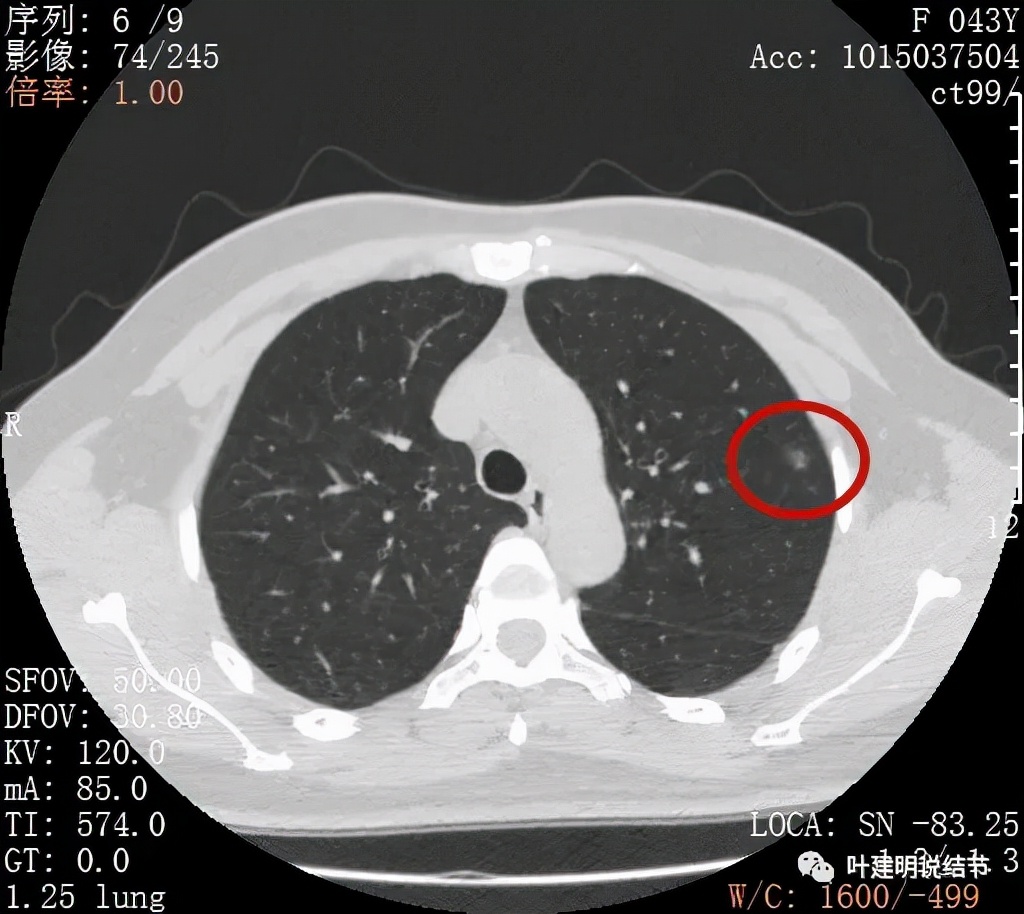

病灶整体密度较低,但轮廓较清,内部密度不大均匀,显得杂乱

不均质的偏低密度磨玻璃结节,轮廓清

上图示病灶内部有高密度点状成分(粉色箭头所指)

同样示内部点状高密度,瘤肺边界清,密度显乱